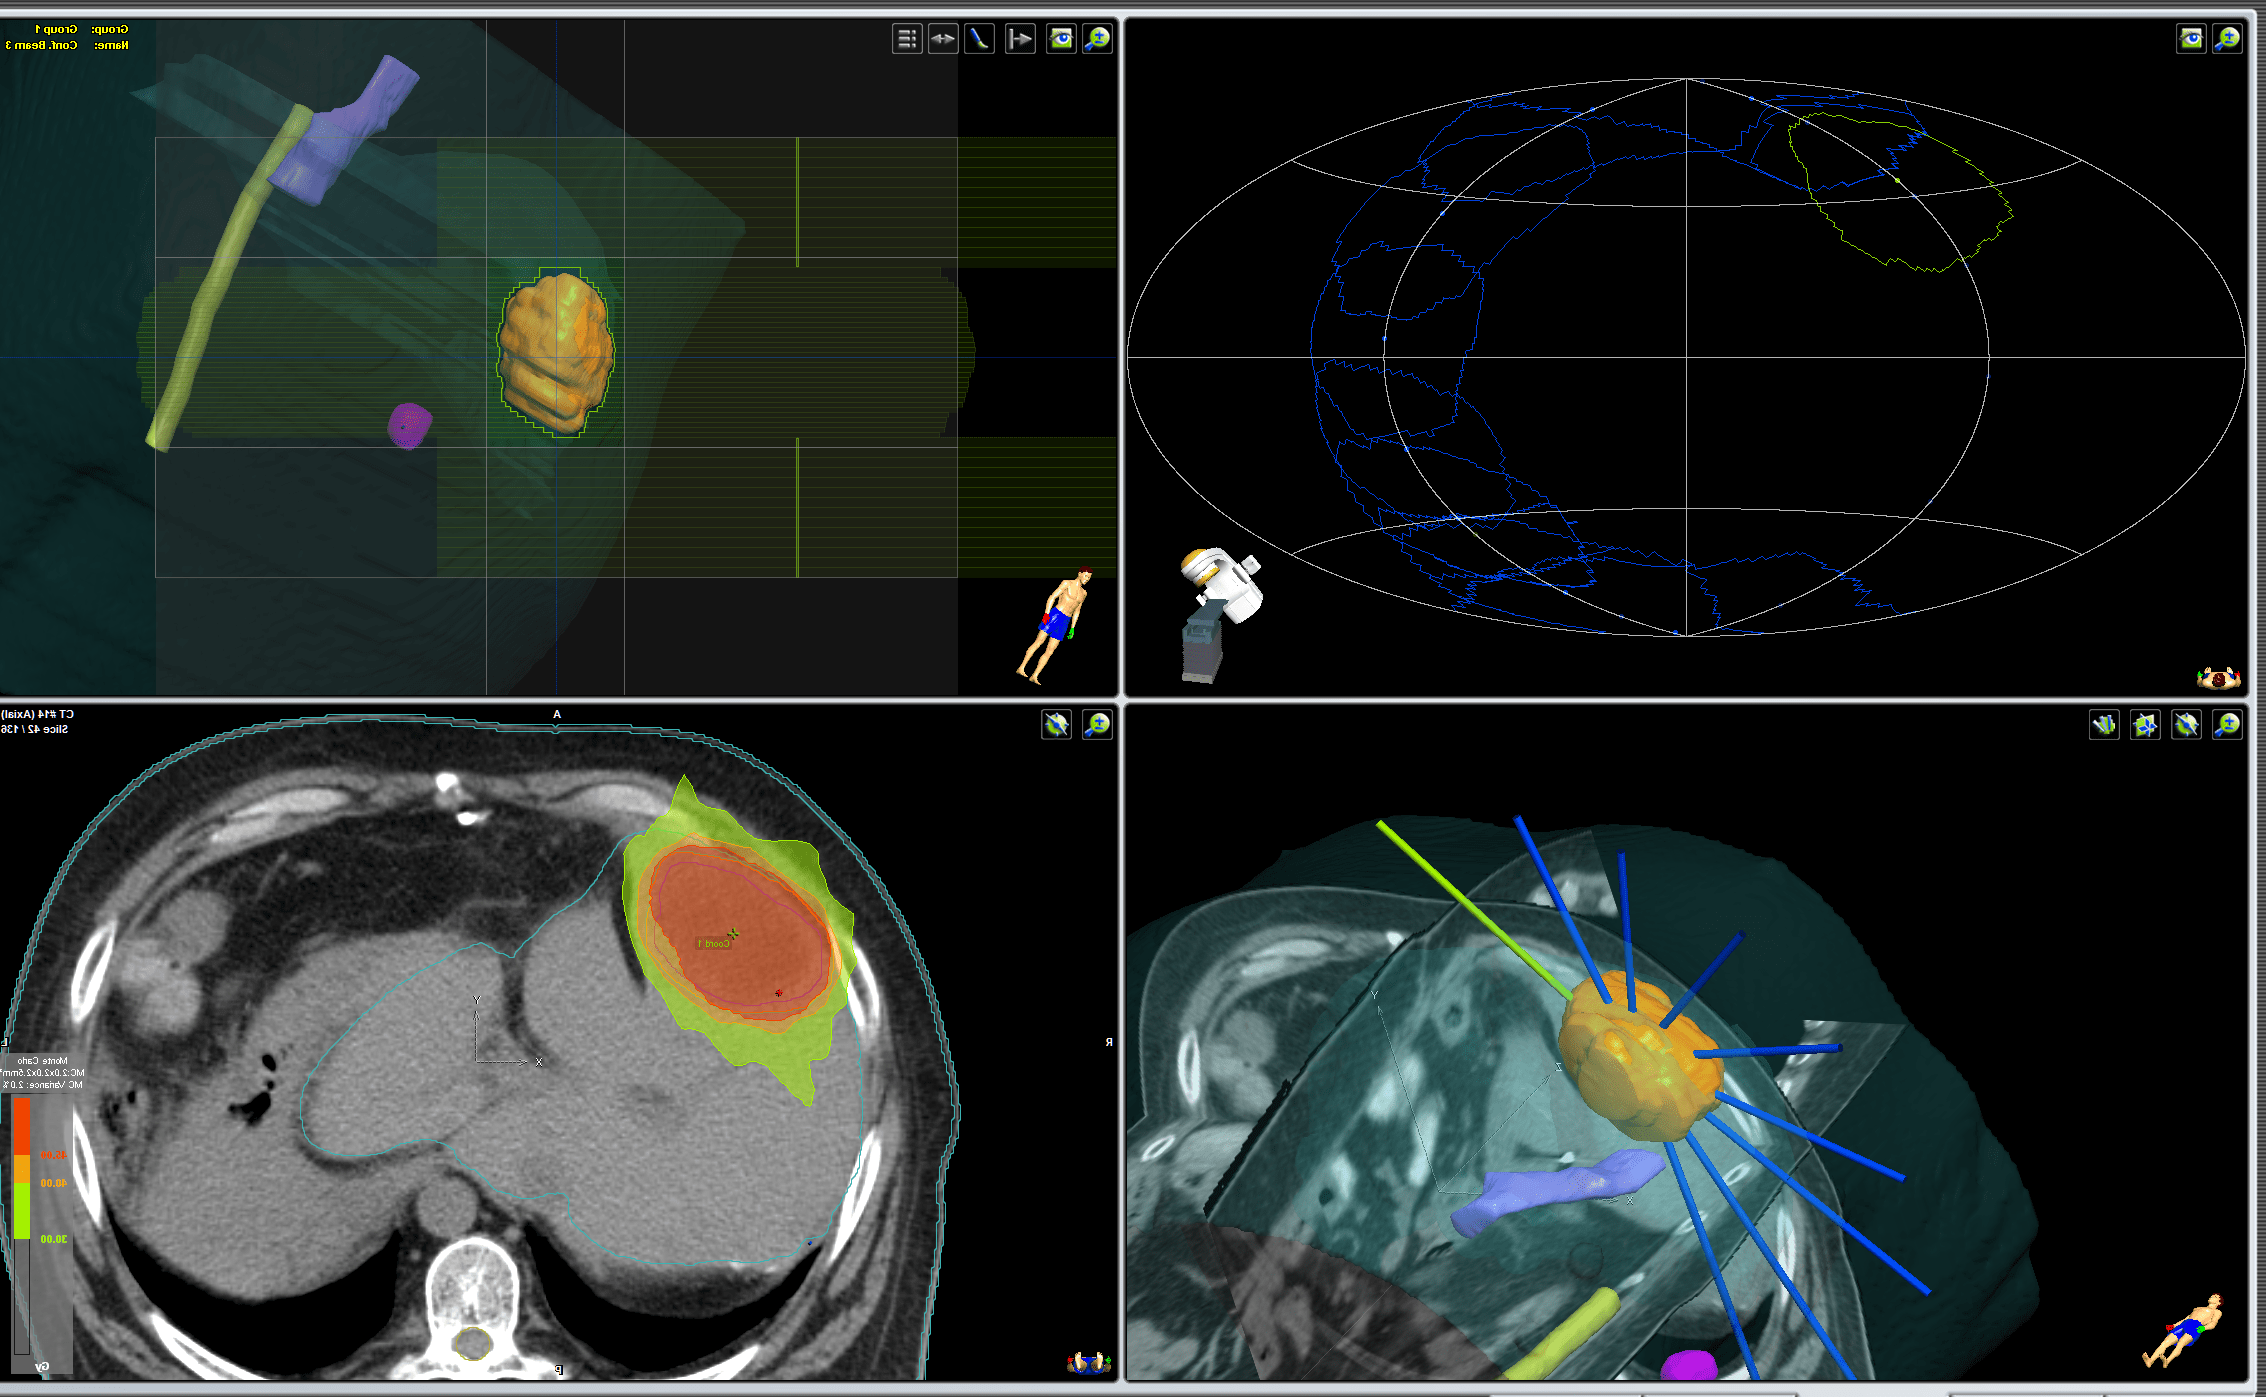

radiografia de tumor en el higado.

Planeación virtual de tumor en el hígado. Físicos médicos y dosimetristas han delimitado los volúmenes blancos y los órganos de riesgo (tejidos sanos circundantes) y calculado la distribución de dosis precisas, así como, las direcciones de los haces de radiación que se apuntarán al tumor.